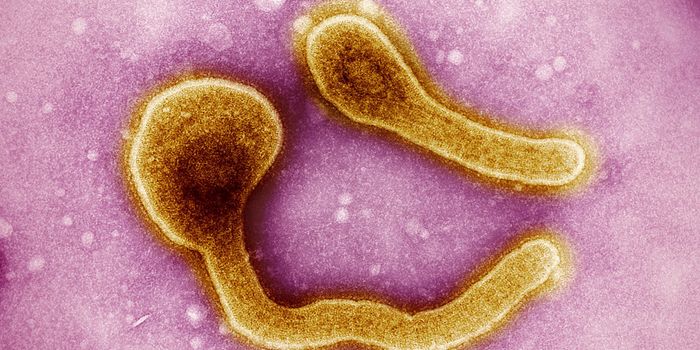

APR 15, 2021Clinical & Molecular DXDuke University scientists have created a highly sensitive Ebola virus portable diagnostic device, 1000 times more sensi ...

APR 29, 2016Clinical & Molecular DXEbola infection and transmission caused a huge international health crisis in 2015 in West Africa, the site of the large ...

FEB 11, 2022MicrobiologyEbola virus has caused several major outbreaks in recent decades. Its high death rate and disturbing symptoms have made ...